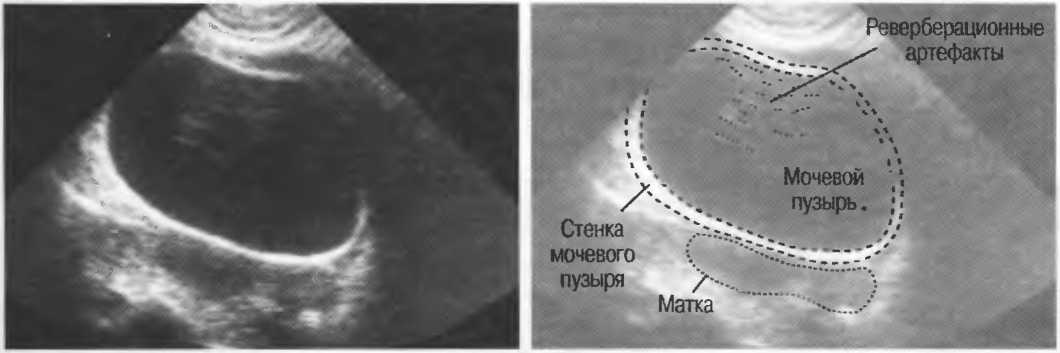

Реверберация |

Отражение ультразвуковых волн назад и вперед между двумя сильно отражающими поверхностями, параллельными или почти параллельными. В этом случае происходит задержка возвращения отраженного сигнала к датчику, в результате чего изображения отражающих поверхностей расположены глубже, чем они есть на самом деле. Это также может проявляться в удвоении или утроении изображения. Например, реверберации могут наблюдаться в передних отделах перерастянутого мочевого пузыря или между параллельными мышцами стенки брюшной полости. |

Артефакты могут определяться в любой кистозной структуре (такой, например, как мочевой пузырь или желчный пузырь) и чаще определяются ближе кпереди, становясь менее выраженными на глубине. Они исчезают или меняют свой характер при изменении положения датчика. Но истинные структуры в кисте, такие как перегородки, сохраняют свое местоположение независимо от положения датчика. Истинные отражения имеют место при наличии сгустка крови, гноя, некротической взвеси, и все это чаще визуализируется по задней стенке: если эти структуры не фиксированы к стенке, они изменяют свое положение при перемене положения тела пациента (рис. 16).

Реверберации

Реверберации имеют место при прохождении ультразвукового луча от одного вида ткани к другому при резко выраженном различии акустического сопротивления этих тканей, например от кишечного газа к печени или ребрам: реверберации могут экранировать ткани, лежащие за газом (рис. 20а).

Реверберации могут полностью менять изображение, создавая линейные структуры или зеркальное отображение. Например, реверберации между параллельными слоями подкожных тканей создают параллельные линейные структуры в мочевом пузыре (рис. 20в).

Рис.20в. При сканировании матки через наполненный мочевой пузырь параллельные датчику слои тканей передней брюшной стенки могут вызывать появление ревербераций, которые определяются как зхоструктуры в передних отделах мочевого пузыря на фоне анэхогенной полости. Поперечный срез (слева) отличается от продольного среза (справа) при изменении положения датчика.